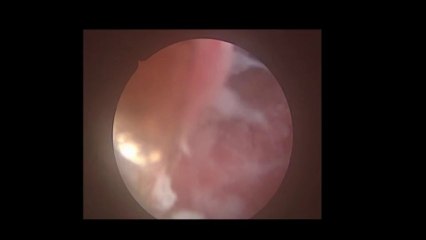

Laparoskopi ile Endometiroma (Çikolata kisti) operasyonu 1 - Prof. Dr. Aydan Biri

Laparoskopi ile Endometiroma (Çikolata kisti) operasyonu 1 - Prof. Dr.